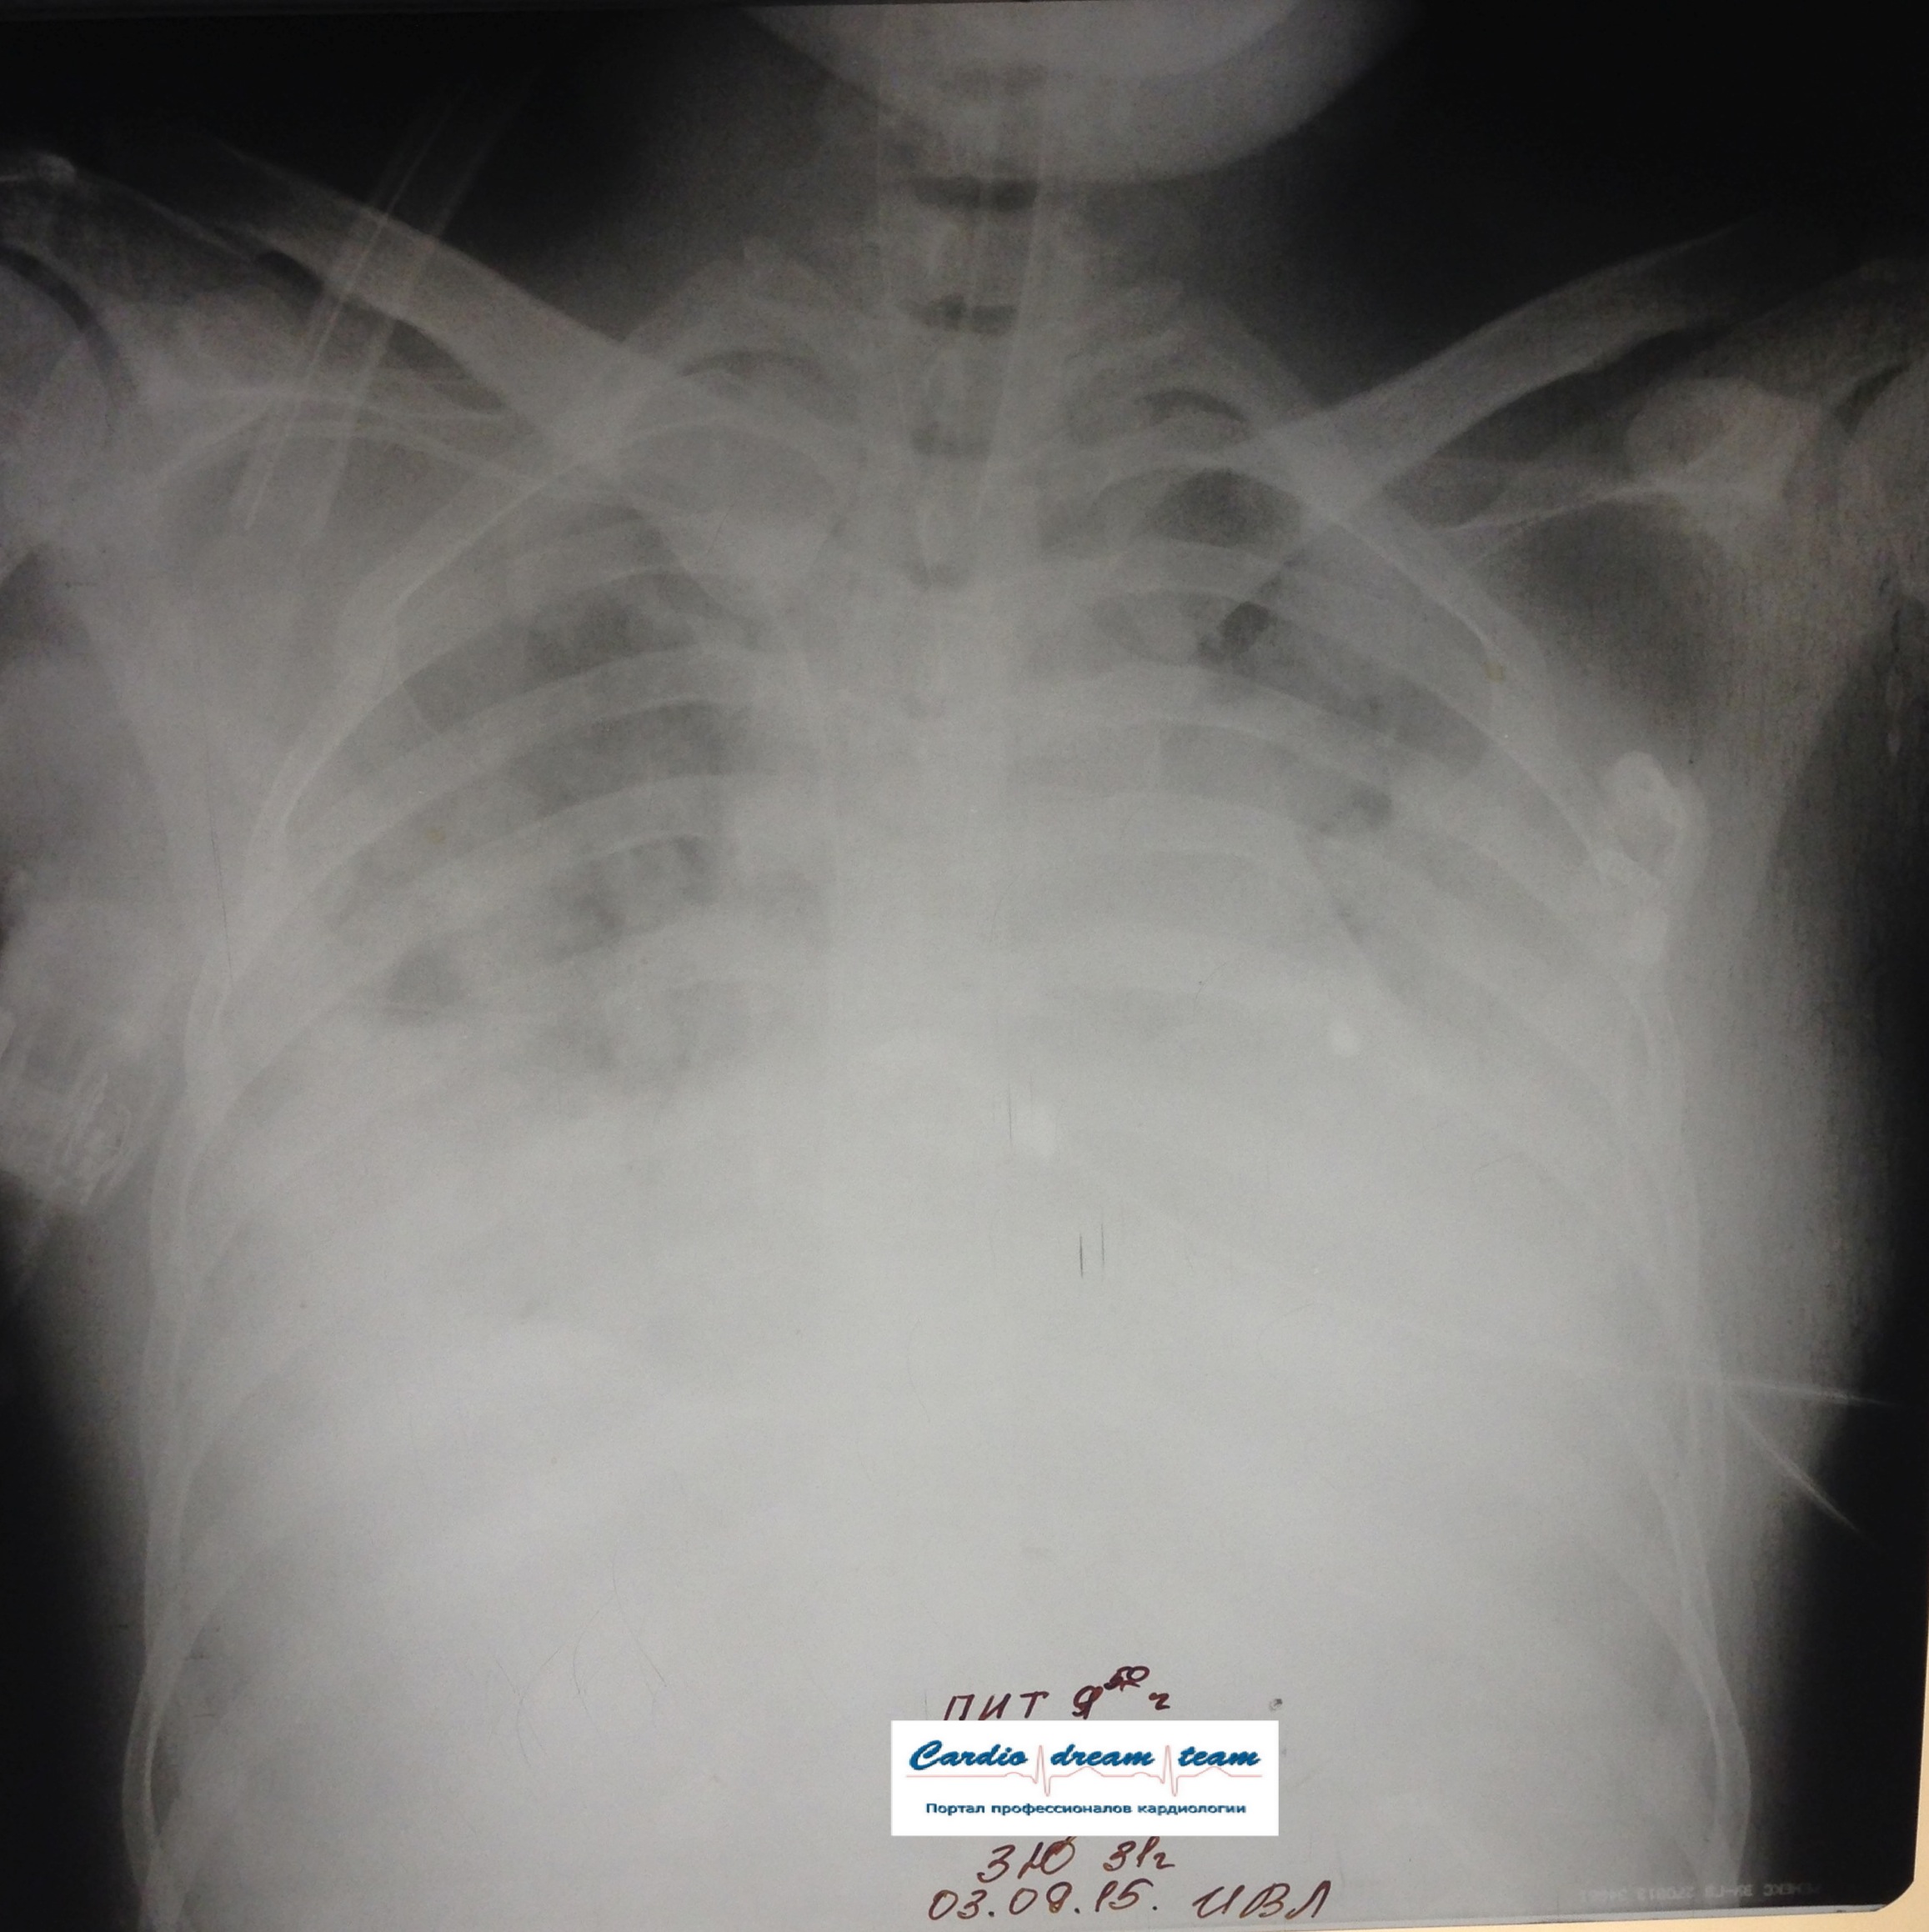

Возникновение и динамика вентилятор - ассоциированной пневмонии.

Вложения:

1-.jpg

1-.jpg [ 713.01 KiB | Просмотров: 50445 ]

2-.jpg

2-.jpg [ 759.1 KiB | Просмотров: 50445 ]

3-.jpg

3-.jpg [ 754.54 KiB | Просмотров: 50445 ]